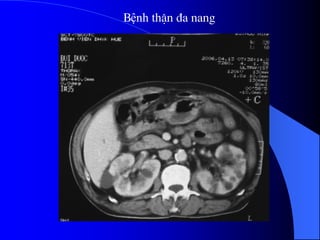

3.5. Tháûn âa nang

Tháûn âa nang laì bãûnh di truyãön.

Nang coï nguäön gäúc tæì nephron. Thæåìng

xaøy ra åí hai tháûn, nãúu tháúy tháûn âa nang mäüt

bãn thç bãn kia coï báút thæåìng kên âaïo hån,

nhæîng nang nhoí hån.

Khoaíng 50% træåìng håüp kãút håüp våïi

nhæîng báút thæåìng khaïc nhæ nang gan, nang

tuûy, nang laïch, tuïi phçnh âäüng maûch naîo.

Bệnh thËn ®a nang

APCD/ Autosomal dominant PolyCystic Disease

ThËn, gan ®a nang